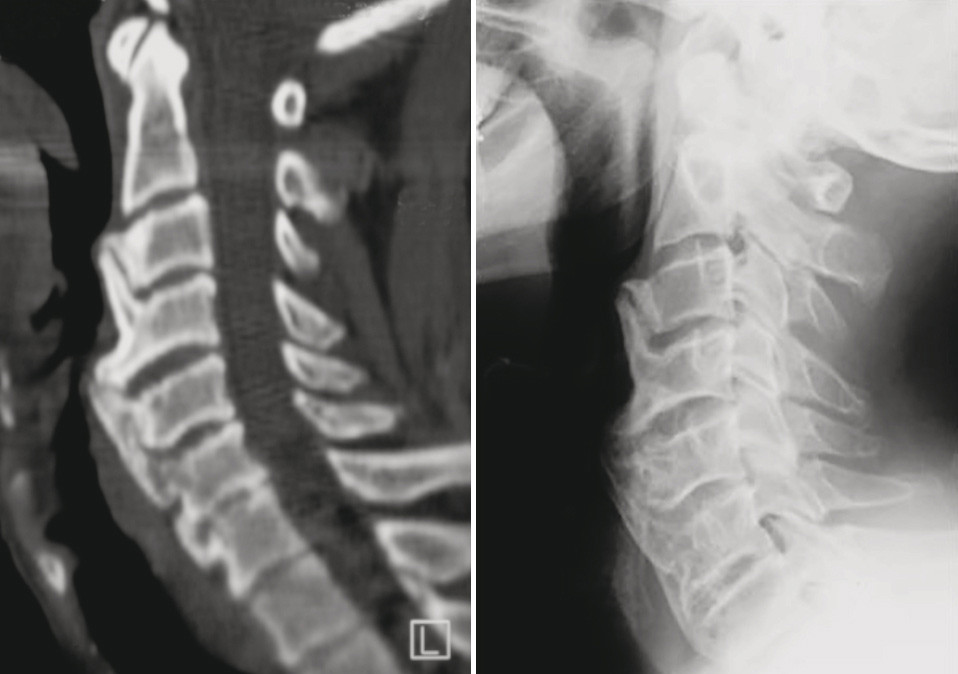

Illustrasjonen viser CT-bilde med rekonstruksjon. Det gir den beste fremstillingen av forandringene. Røntgen cervikalcolumna viser beinete påleiringer på halsvirvlene. Funksjonsbilder med bøy og strekk kan vise innskrenket bevegelighet.